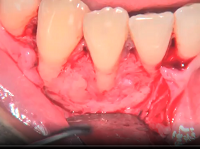

Oral Suergery (Zerodonto Dentistry) 2018

Spécialités : Stomatologie